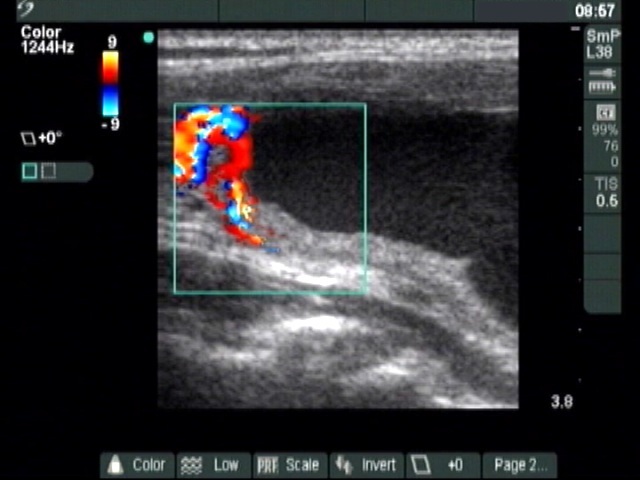

Ultrasonography: The thyroid was echonormal. A large cystic nodule composed of multiple chambers occupied almost the entire right lobe. Several fibrotic bundles dividing the chambers of the cyst were ruptured. The nodule presented halo sign and perinodular blood flow.